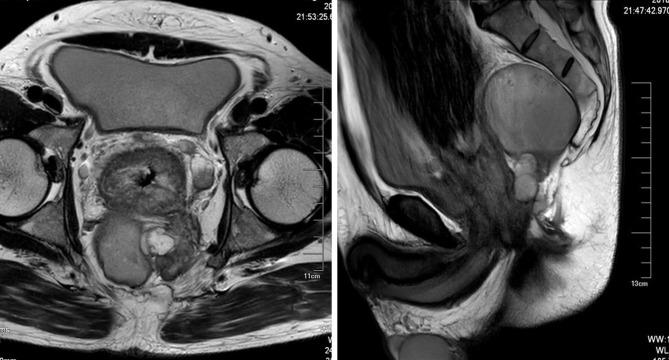

直肠黏液腺癌侵犯直肠后皮样囊肿:一例报告

Rectal Mucinous Adenocarcinoma Invading Retrorectal Dermoid Cysts: A Case Report.

Rectal mucinous adenocarcinoma is a subtype of colorectal adenocarcinoma, which is more aggressive and prone to invade adjacent normal organs or tissues compared with non-mucinous adenocarcinoma. Retrorectal dermoid cyst is a rare congenital disease, which usually are benign but with a potential for malignant degeneration. In this article, we report a case which presented a rectal mucinous adenocarcinoma invading into retrorectal dermoid cysts, indicating that besides adjacent normal organs or tissues, malignancies can also invade adjacent tumors, making their diagnosis and management more complicated. In such cases, double primary tumors should be considered, and they should be removed surgically.

摘要

直肠黏液腺癌是结直肠癌的一种亚型,与非黏液腺癌相比,其侵袭性更强,更容易侵犯相邻的正常器官或组织。直肠后皮样囊肿是一种罕见的先天性疾病,通常为良性,但有恶变的可能。在本文中,我们报告了一例直肠黏液腺癌侵犯直肠后皮样囊肿的病例,表明除了相邻正常器官或组织外,恶性肿瘤也可侵犯相邻肿瘤,使其诊断和治疗更加复杂。在这种情况下,应考虑双原发肿瘤,并应手术切除。